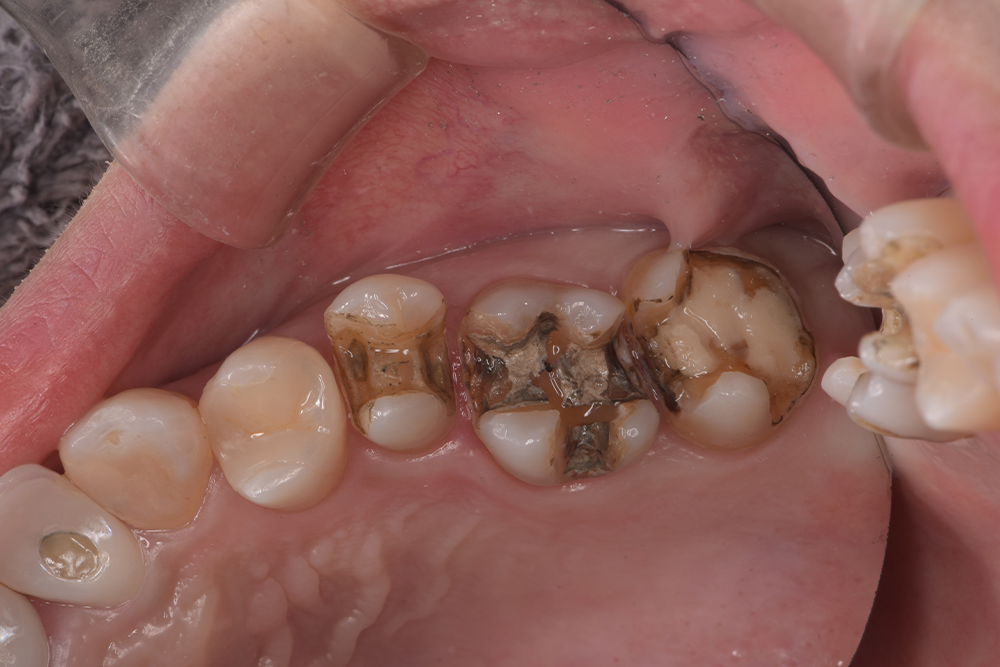

| 治療経過 | 銀歯の隙間にフロスが引っかかるとのことで治療介入となった。 銀歯の下は全て虫歯になっており、今後虫歯のリスクを軽減させることを目的として、歯への接着力、清掃性に優れたセラミックを用いた修復方法を選択した。 |